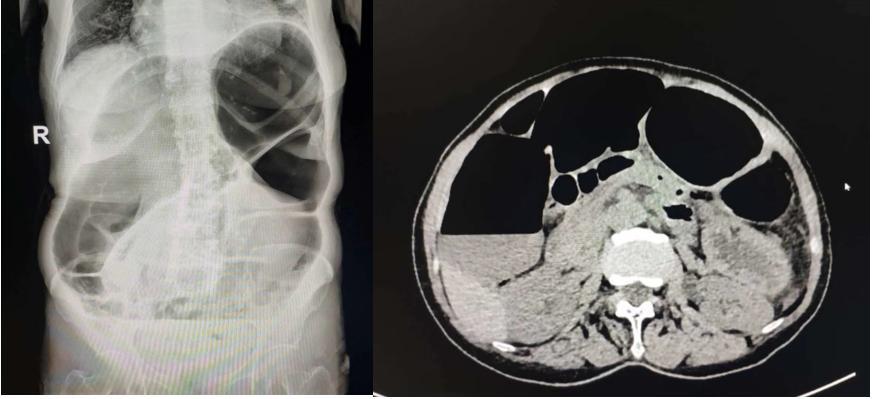

据悉,患者钟女士,今年76岁高龄,家属诉近2年经常发现患者“大腹便便”,患者自诉近1月腹痛、腹胀较前明显加重,而且不能自行缓解,故来我院就诊。门诊在完善腹部立位平片拍摄后,考虑为不全性肠梗阻,将患者立即收住入院。

入院后徐立副主任医师在查看患者时发现腹部膨隆明显,可见明显肠型,叩诊呈鼓音,非移动性浊音,立即安排禁食、胃肠减压、肛管排气、补液等治疗,在与曾伟副主任医师查看腹部CT后高度怀疑存在乙状结肠扭转,一边电话急请胃肠外科会诊,一边与患者及家属沟通可能的治疗方案选择,鉴于患者高龄,身体一般状况尚可,没有出现感染等临床表现,也没有出现电解质紊乱,积极建议先尝试内科保守治疗,通过内镜技术解除乙状结肠扭转。